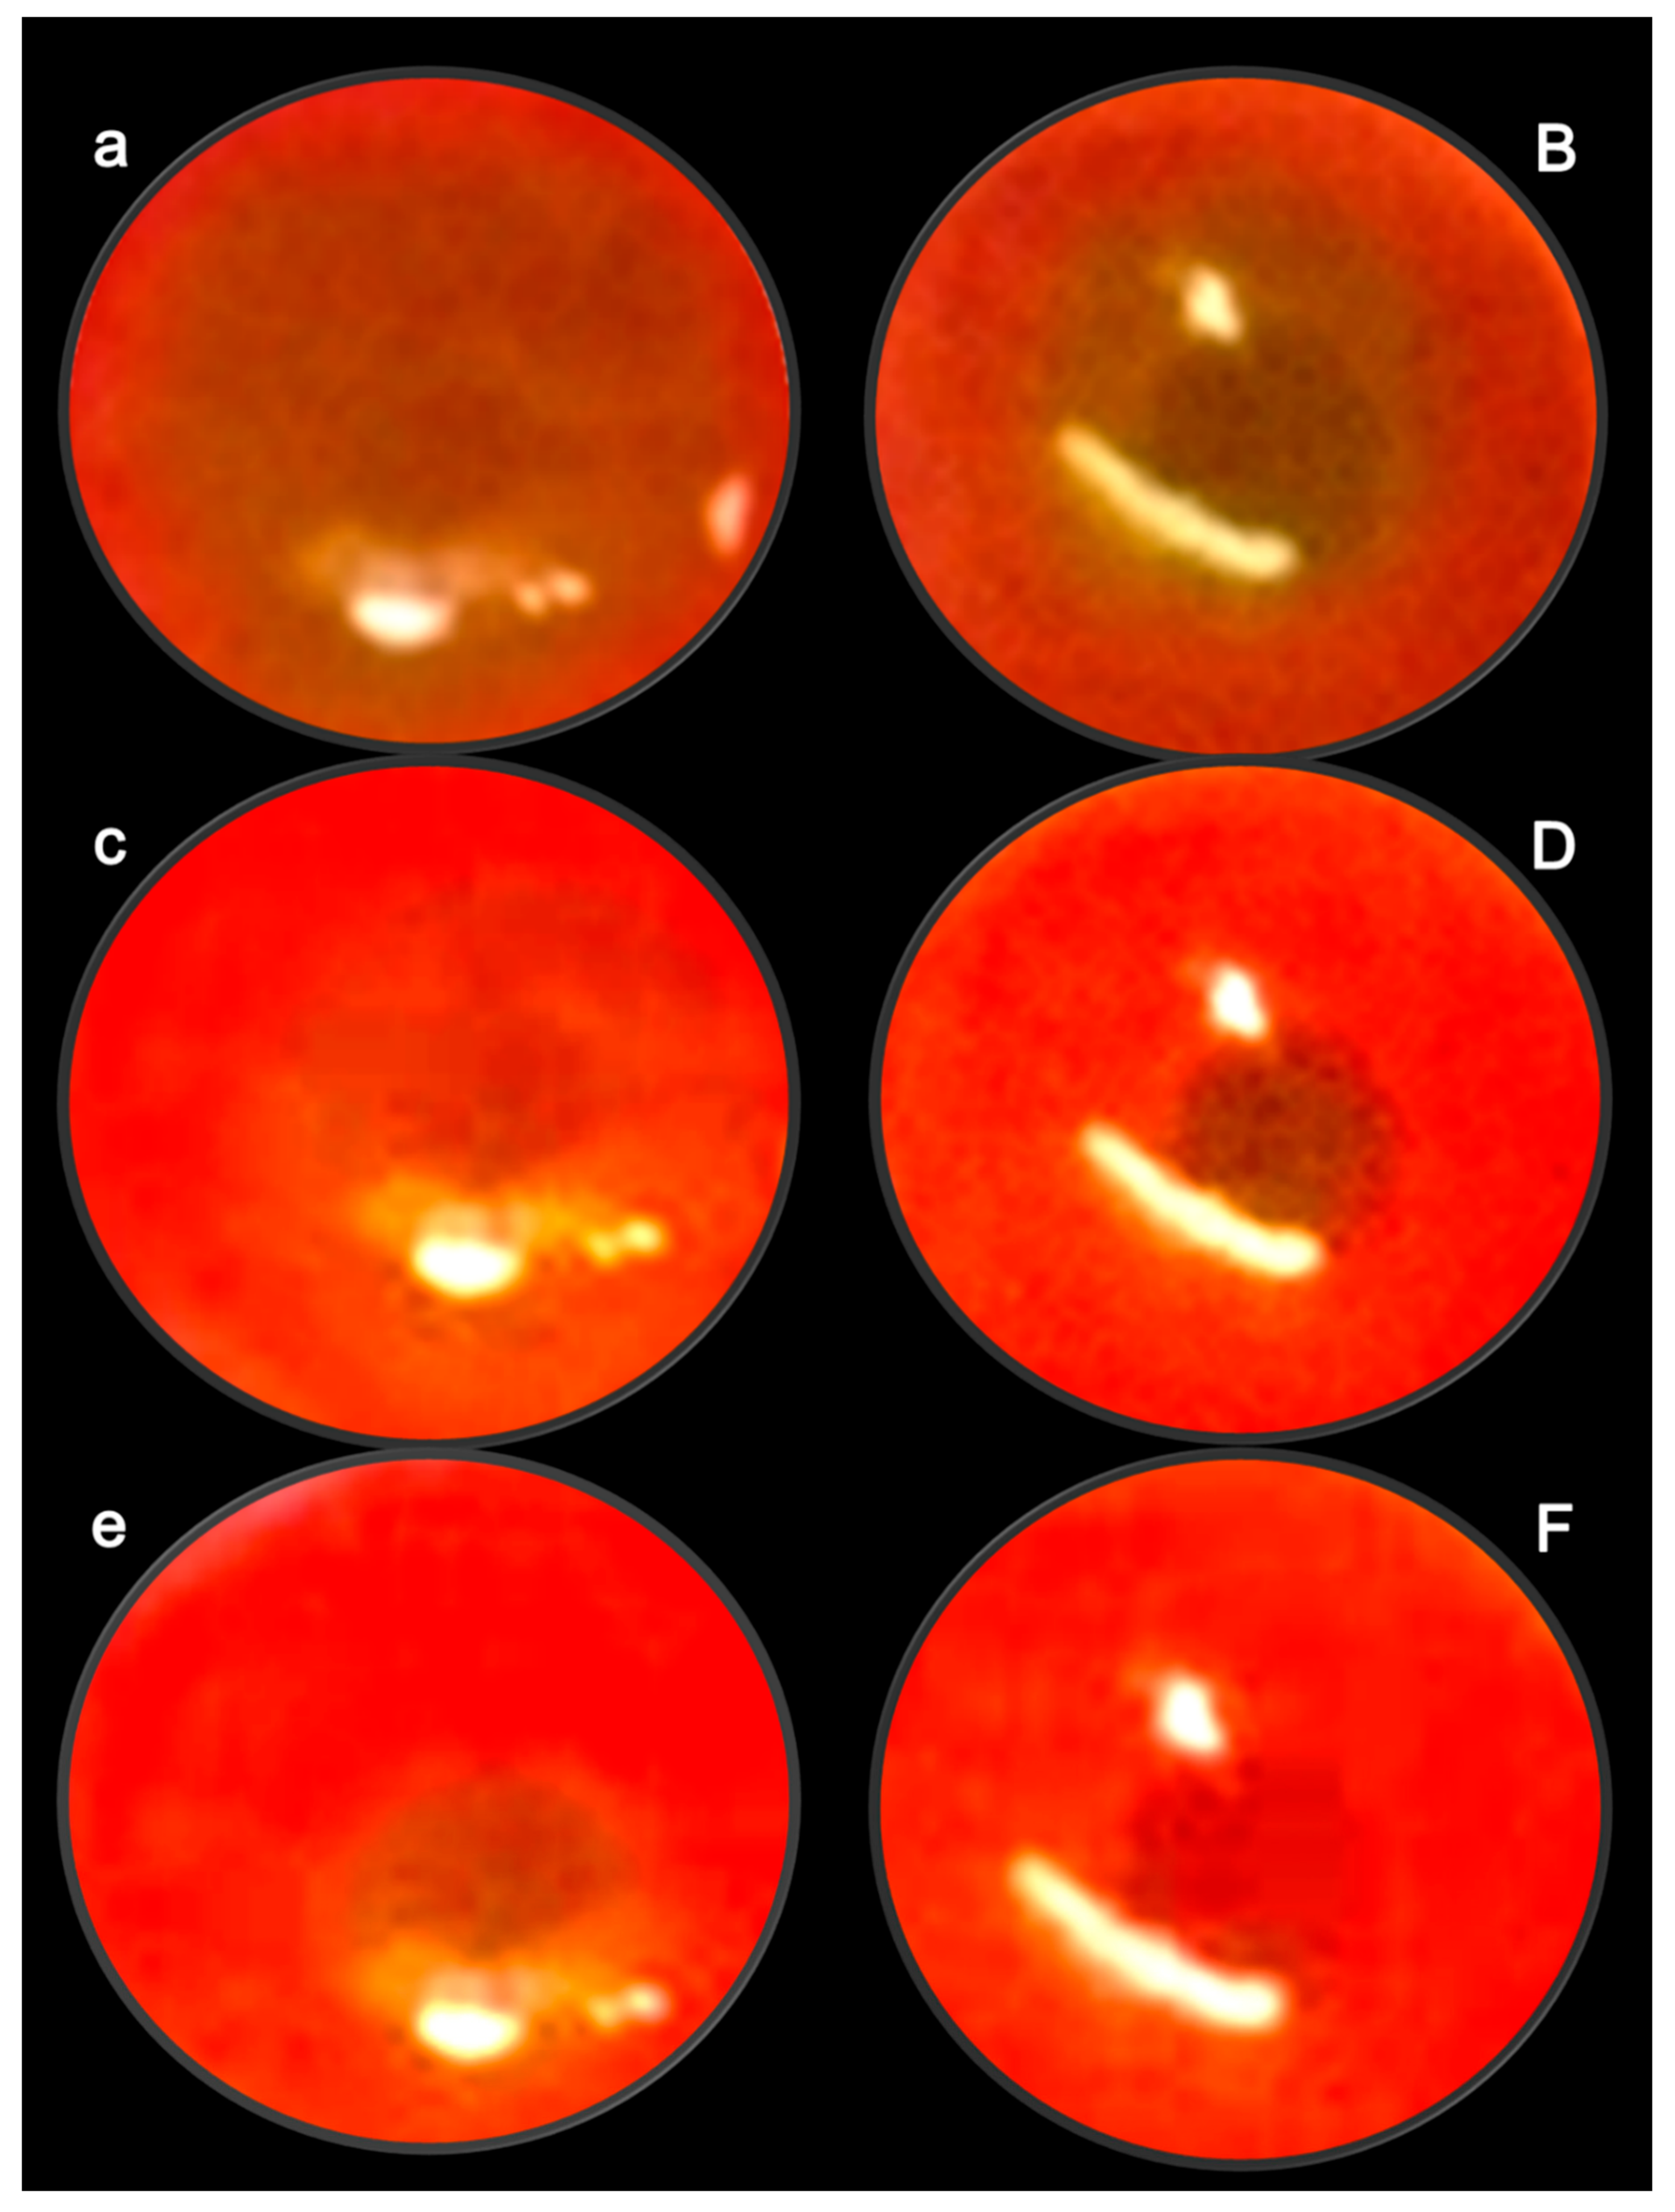

- Zlatar, M.; Kokot, A.; Vuletic, L.B.; Masnec, S.; Kralj, T.; Perisa, M.M.; Barisic, I.; Radic, B.; Milanovic, K.; Drmic, D.; et al. BPC 157 as a therapy for retinal ischemia induced by retrobulbar application of L-NAME in rats. Front. Pharmacol. 2021, 12, 632295. [Google Scholar] [CrossRef]

- Masnec, S.; Kokot, A.; Zlatar, M.; Kalauz, M.; Kunjko, K.; Radic, B.; Klicek, R.; Drmic, D.; Lazic, R.; Brcic, L.; et al. Perforating corneal injury in rat and pentadecapeptide BPC 157. Exp. Eye Res. 2015, 136, 9–15. [Google Scholar] [CrossRef] [PubMed]